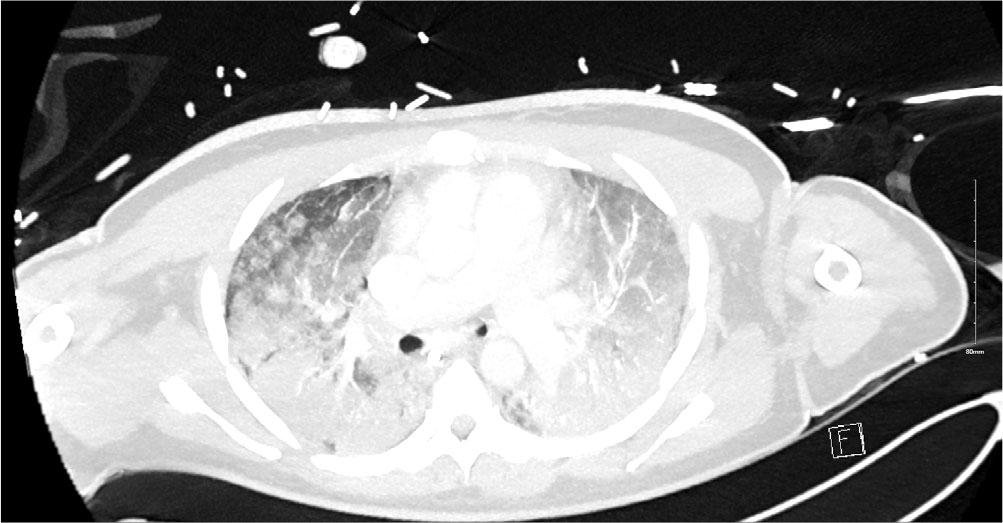

After receiving a course of methylprednisolone (1gm × 3), cyclophosphamide 500mg I.V. and Rituximab 1g the patient improved [2]. This was a transient effect (likely the effect of methylprednisolone) however and on day 15 of admission FiO2 requirements climbed to 1.00 and once again the PF ratio dropped to 9kpa. The patient was unresponsive to prone positioning on this occasion and with the employment of lung protective ventilatory protocols adequate ventilation was difficult to maintain. Given the significant deterioration a repeat CT scan was performed. This showed dense bilateral infiltrates which had significantly worsened since the first CT (Figure 2). The infiltrates were much more extensive throughout both lungs in keeping with ARDS and possible organizing pneumonia. MDT discussion took place, and a decision was made to support with VV ECMO as the pathophysiology was felt to be potentially reversible.

CT Thorax on Day 15 after clinical deterioration showing dense bilateral infiltrates throughout both lung in keeping with ARDS and possible organizing pneumonia. There was no pneumothorax or pleural effusions.